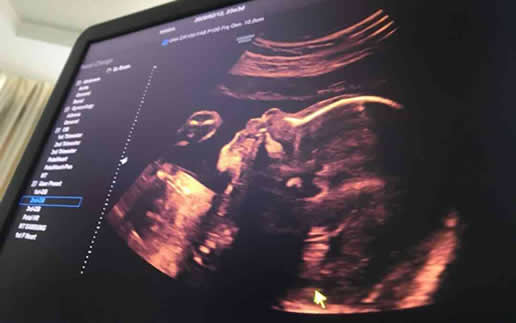

孕妇在怀孕期间进行四维彩超是非常重要的检查方式。通过四维彩超可以观察胎儿的生长发育情况,并及时发现一些可能出现的问题。...

相比于普通B超,四维彩超检查并非每位孕妇都要做,但其优点在于能够清晰的观察宝宝的生长发育情况,是早期诊断胎儿有无先天性畸形的重要技术...

四维彩超一般是在怀孕24周左右进行检查,不需要空腹,在检查前可以正常吃饭,且不会影响到检查结果。但是部分胎儿可能不是特别配合,容易导致四维彩超检查不是特别准确。...

孕期四维检查的最佳时间通常是怀孕22-24周。孕期22-24周这个时候,胎儿的骨骼发育较完善,能够清晰地显示出胎儿的外观和动态。...

一般来说,四维彩超检查时间大概在怀孕22周到26周之间,如果孕妇在这个阶段检查结果一切都正常,那么后期胎儿畸形的概率很低。...